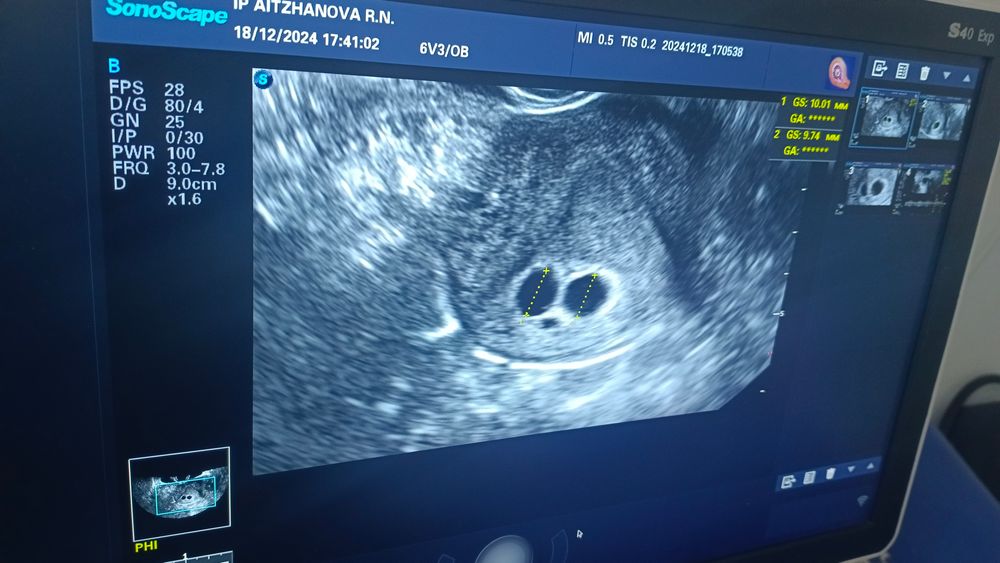

Жм есть хотя бы? И какие размеры пя?

Желточных мешочков тоже не видно, может овуляция была позже и срок меньше тогда🤷‍♀️ У меня на сроке 5+3 видели только ПЯ, ЖМ и эмбриона так же не было, а в 6+4 уже давали слушать сердечко